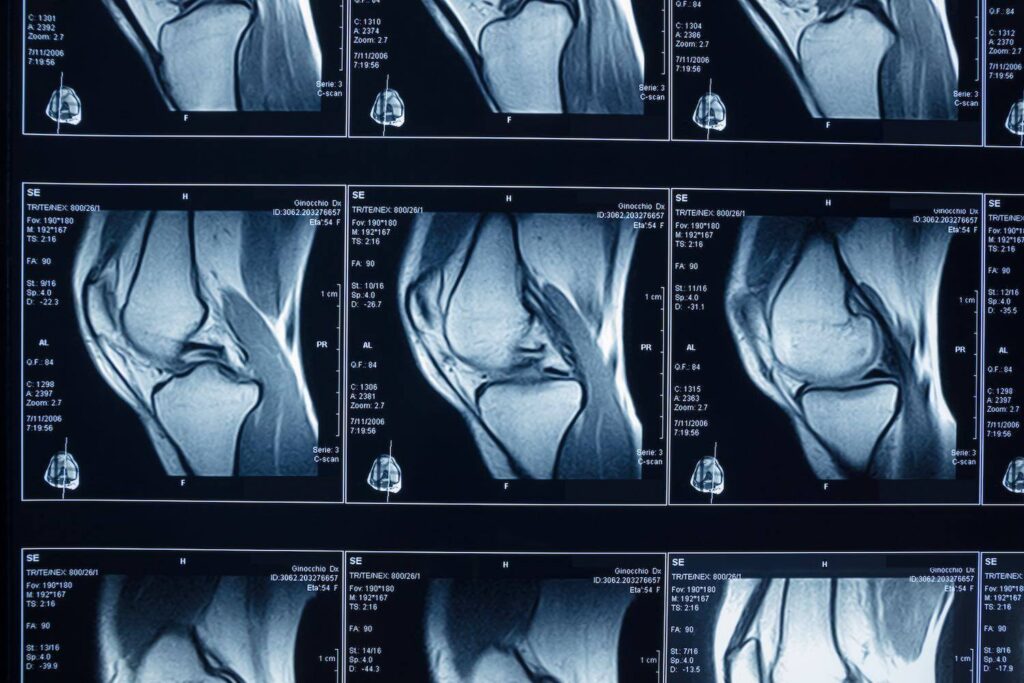

Bis ins letzte Detail: Die Kernspintomografie

Erhärtet sich in der körperlichen Untersuchung der Verdacht auf eine Schädigung der Menisken, wird Ihr Arzt diesen durch eine Kernspintomografie (MRT) absichern. So lässt sich das Weichteilgewebe des Knies (Bänder, Menisken, Muskeln etc.) hochauflösend darstellen. Während sich ein gesunder Meniskus im MRT als durchgehende schwarze Struktur zeigt, sind beim Verschleiß hellere Flecken innerhalb des Meniskus sichtbar.

Ein Riss ist als deutlicher heller Streifen erkennbar, der in der Regel Kontakt zu mindestens einer Oberfläche des Meniskus hat. Ergänzend kann Ihr Arzt im Einzelfall Röntgenbilder anfertigen lassen, um knöcherne Begleitverletzungen insbesondere bei traumatisch bedingten Knieschmerzen auszuschließen.